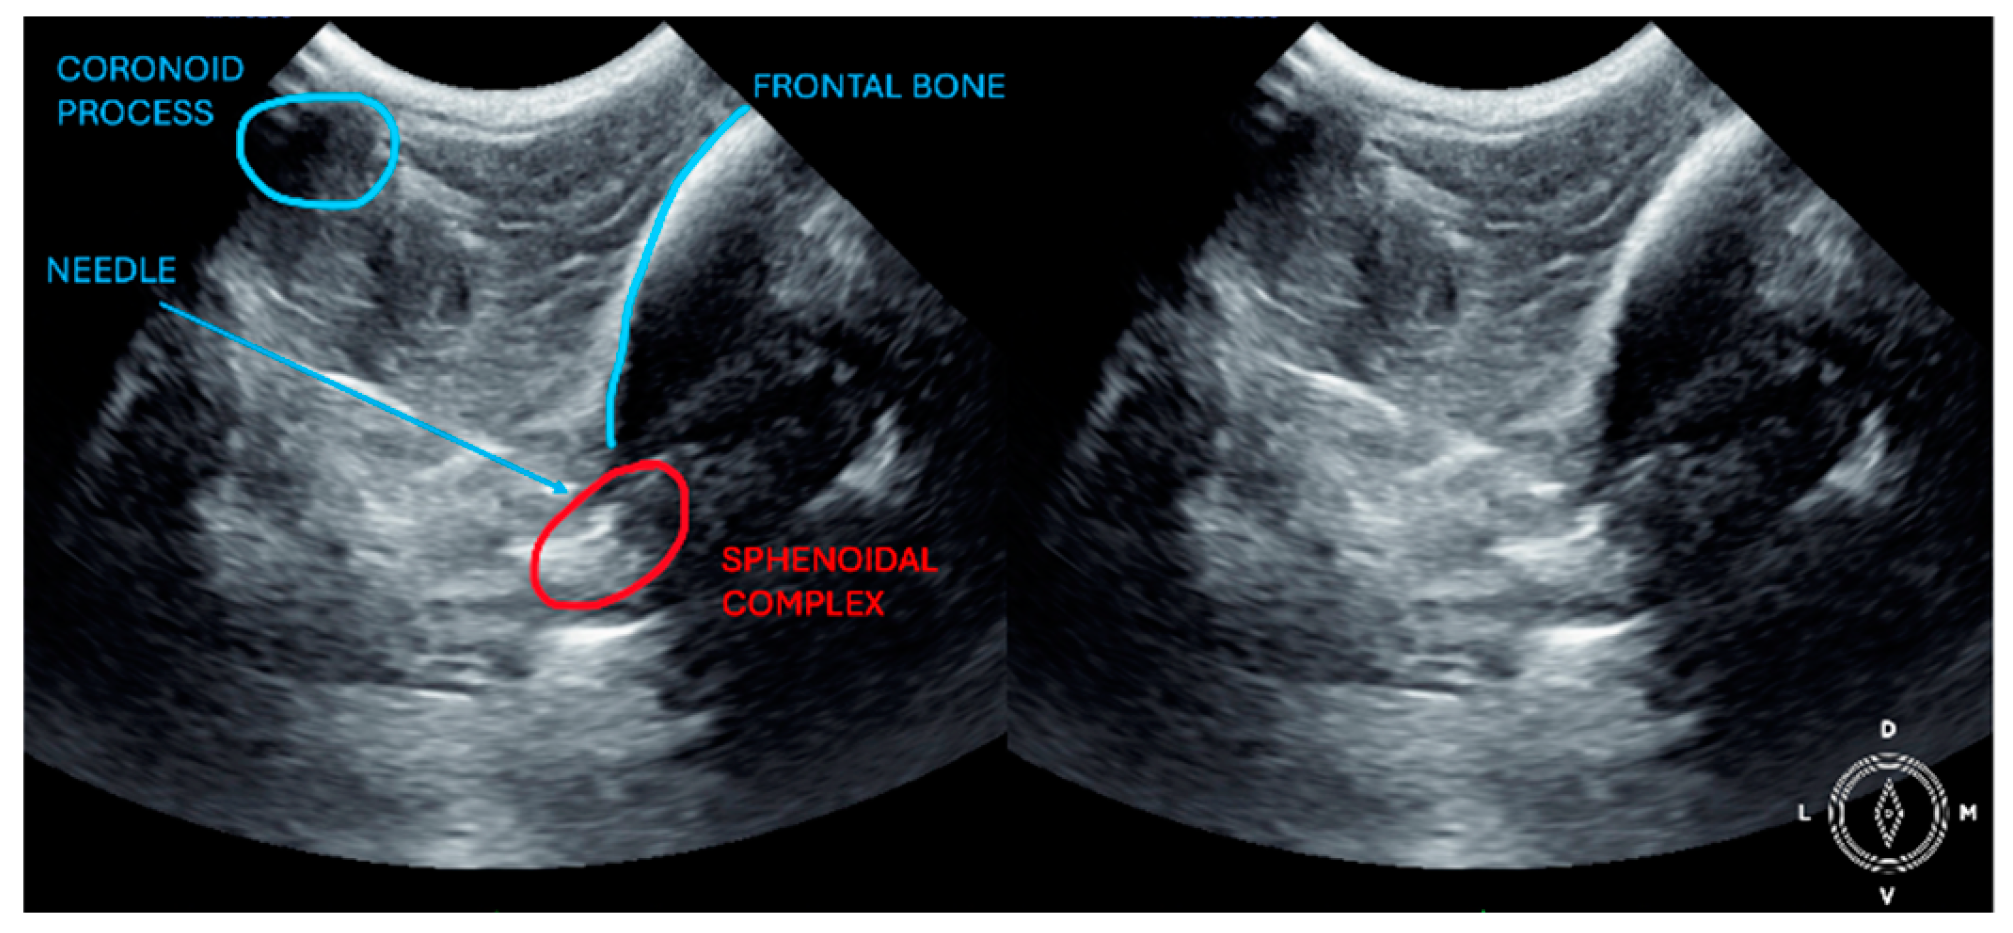

The ultrasound probe was positioned over the temporal region immediately caudal to the orbital ligament to obtain a transverse view of the caudal portion of the pterygopalatine fossa for both approaches. Slight tilting movements adjusted the probe until the following structures were identified: the frontal bone was observed as a hyperechogenic continuous line, which in the deep aspect of the pterygopalatine fossa showed an irregular structure consistent with the sphenoidal complex (optic canal, orbital fissure, and rostral alar canal). The coronoid process was also identified as a sharp, small, strongly reflective, hyperechogenic structure casting a strong acoustic shadow through the fossa (Figure 1 and Figure 2).

Description of the temporal approach: The needle was inserted using an in-plane approach, from the medial aspect of the temporal region in a ventral direction until its tip was located close to the sphenoidal complex (Figure 1), where the calculated volume was injected.

Figure 1. Position of the probe and needle. Ultrasound image of the temporal approach, where the anatomic landmarks can be identified. The microconvex ultrasound probe is placed on the temporal region, caudally to the orbital ligament, in a transversal position.